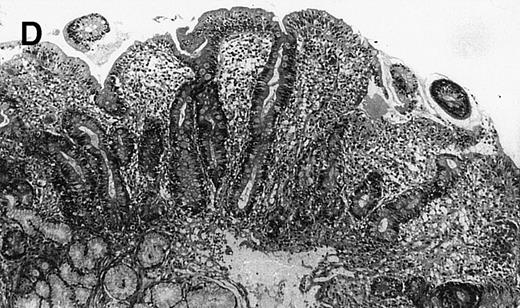

(A) Case no. 1. (B and C) Case no. 2. (D) Case no. 3. (E) Case no. 4. (A, B, D, and E) Duodenal biopsies showing total villous atrophy with crypt hyperplasia and infiltration of lamina propria by nonatypical inflammatory cells (Hematoxylinandeosin; original magnification × 10). (C) Jejunal biopsy showing villous atrophy and ulcerations with regenerative epithelial changes on the border of ulcerations; no evidence of lymphoma.

The 4 patients with complicated CD had duodenal biopsies consistent with untreated CD; total villous atrophy, intraepithelial lymphocytosis, crypt hypertrophy, and inflammation of lamina propria with benign-appearing lymphocytes, plasma cells, and eosinophils were observed. There was no histological evidence of lymphoma. Patient no. 4 also had biopsies performed at the border of duodenal ulcerations that showed epithelial erosions without histological evidence of lymphoma.